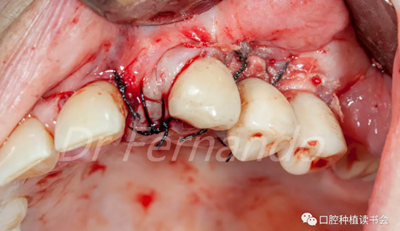

在骨粉上方覆蓋 Osgide? 可吸收膠原膜(Curasan?-科盧森) ,用絲線嚴(yán)密關(guān)閉傷口(圖 22 )

圖22 植骨區(qū)覆蓋可吸收膠原膜,關(guān)閉創(chuàng)口